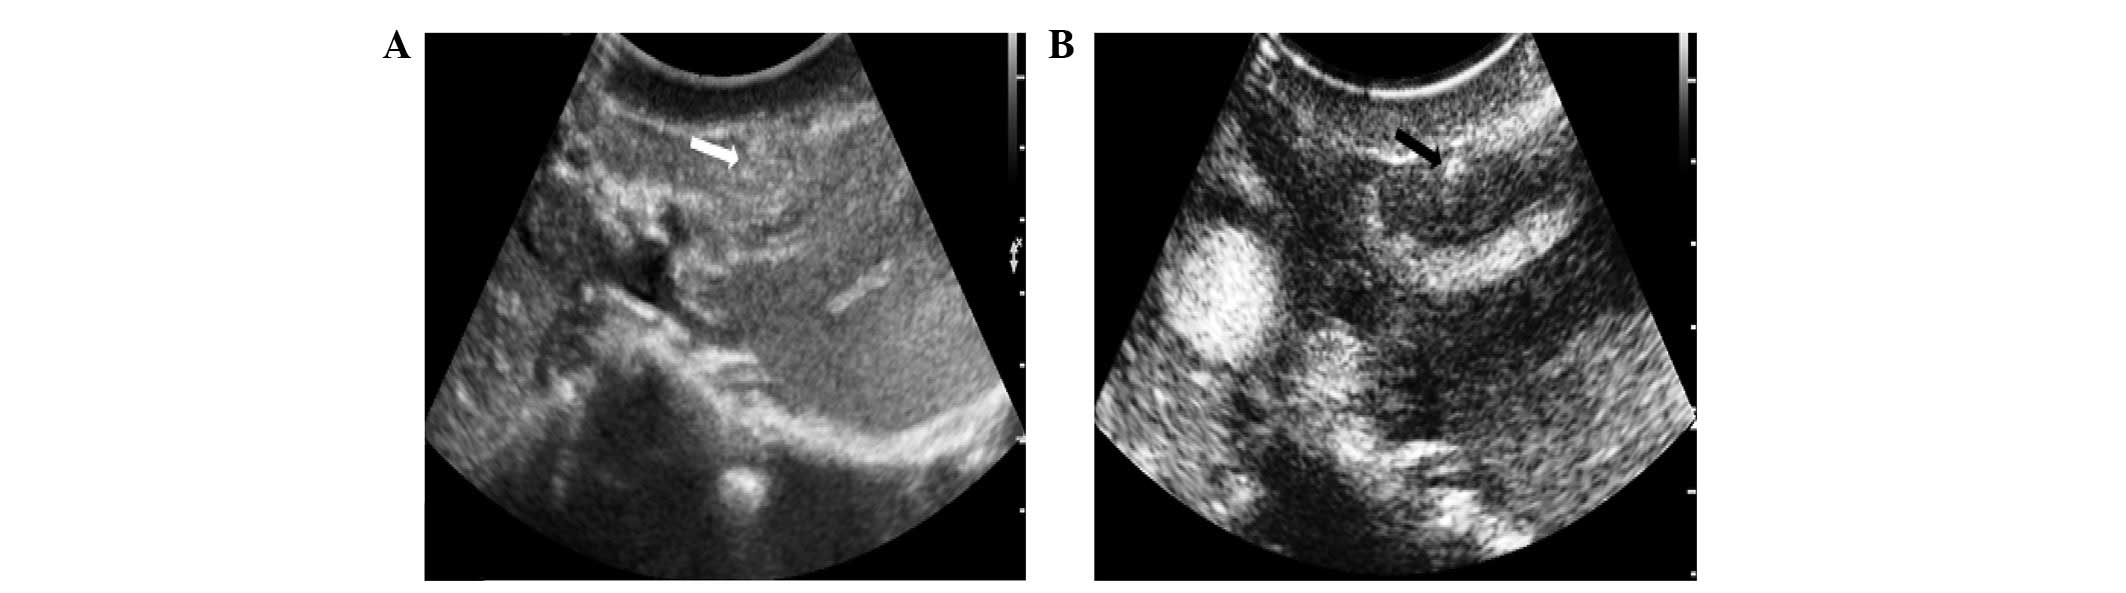

A total of twenty-one lesions were detected using

conventional US (Figs. 1 and

2), while nineteen lesions

remained undetected. The detection rate of conventional US in

pancreatic trauma was 52.5% (Table

III). The pancreatic lacerations appeared as slit- or

stripe-shaped hyperechoic, hypoechoic or anechoic areas on the

baseline US image. The pancreatic contusions appeared as lamellar

hyperechoic or hypoechoic areas with unclear margins in the

parenchyma on conventional US images.

Following the injection of the contrast agent, 34

lesions were detected and 6 lesions remained undetected by CEUS.

The detection rate of CEUS in pancreatic trauma was 85%, which was

significantly higher than that of conventional US, (P<0.05;

Table III). The six lesions that

were not revealed by CEUS were MPD− lesions. The

pancreatic lacerations showed no enhancement in the two phases,

however a high enhancement was observed in the two phases due to

active bleeding (Figs. 1 and

2). The pancreatic contusion

showed low enhancement in the two phases. The margins of the

pancreatic injuries were clearly observed compared with the normal

parenchyma by CEUS.

The lacerations were visible as low-attenuation

lines oriented perpendicularly to the long axis of the pancreas

(Fig. 1). The diagnosis of a